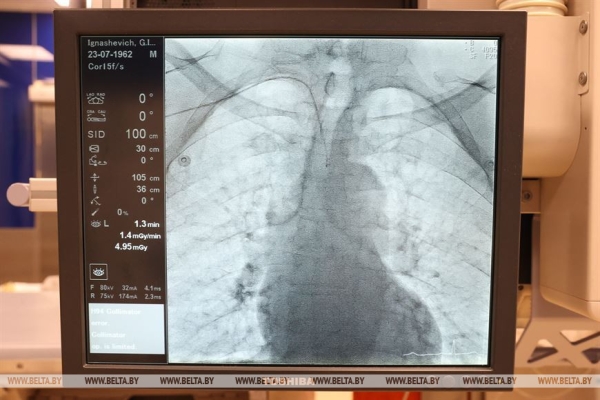

«Солигорская центральная районная больница является одним из четырех межрайонных центров Минской области. В нашем составе функционирует 26 межрайонных отделений и кабинетов. Мы обслуживаем Солигорский район с 128,4 тыс. населения, из них чуть более 109 тыс. — это городские жители, чуть более 18 тыс. — сельские. Также мы оказываем помощь пациентам из семи закрепленных за нами районов Минской области, это практически все районы юга Минской области. Среди них Клецкий, Копыльский, Несвижский, Слуцкий, Стародорожский, Любанский районы. По этим районам мы являемся центром по оказанию высокотехнологичной медицинской помощи, в первую очередь пациентам с острым коронарным синдромом — с инфарктом миокарда, с острым нарушением мозгового кровообращения. Работаем в круглосуточном режиме. В состав центра входит кардиологическое отделение для пациентов с инфарктом миокарда, отделение для пациентов с острым нарушением мозгового кровообращения, кабинет компьютерной магнитно-резонансной томографии и отделение интервенционной радиологии. Мы оказываем помощь на высоком уровне, это было отмечено мониторинговой группой, а также свидетельствуют награды, которые получают наши специалисты. Например, в этом году наш кабинет интервенционной радиологии получил награду «Прорыв года», — рассказал главный врач Солигорской ЦРБ Александр Кисель.

Рентгенэндоваскулярный хирург, заведующий кабинетом ангиографии и руководитель Южного межрайонного центра Минской области Александр Янукович гордится тем, что его отделение, став в 2014 году первым отделением районной эндоваскулярной хирургии в стране, сейчас является крупным специализированным центром. «Мы выполняем практически весь спектр вмешательств, который можно предложить пациентам на уровне районной больницы. Мы — это большой сплоченный коллектив, работающий уже 9 лет. У нас оказывается помощь пациентам южной части Минской области, а это 360 тыс. населения. Основная наша задача — оказание помощи пациентам с ишемической болезнью сердца, с ишемическим инсультом и цереброваскулярными болезнями. Мы также являемся межрайонным центром по имплантации электрокардиостимуляторов, этой программой занимаемся в течение последних двух лет. Прооперировано уже порядка 150 пациентов. Они обслуживаются у нас же — на базе центра организован кабинет контроля кардиостимуляторов. Также с гордостью мы можем сказать, что являемся единственным центром районного уровня в стране, который выполняет вмешательства по ишемическому инсульту, вмешательства на сосудах шеи. Кроме того, являемся межрайонным центром по сосудистой хирургии. Поэтому мы многофункциональная, многопрофильная, многоуровневая структура. Например, сегодня у нас 6 плановых операций, две из них — это постановка кардиостимулятора, три пациента с ишемической болезнью сердца, один из них готовится к кардиологическому вмешательству в РНПЦ кардиологии, два — с перенесенным в прошлом инфарктом. В любой момент к нам могут доставить пациента с ишемическим инсультом, например, а это уже нейрохирургическая помощь. В среднем за сутки мы обслуживаем 10 пациентов. С нового года через нас прошло уже порядка 900 пациентов, и такими темпами за год мы получим цифру в 1-1,6 тыс. пациентов», — рассказал Александр Янукович.

Кабинет ангиографии ЦРБ в Молодечно оснащен ангиографическим аппаратом высокого класса, который позволяет проводить операции на сосудах любой локализации — от головного мозга до верхних и нижних конечностей. «В основном мы занимаемся острой и хронической патологией сосудов сердца. Нередко приходится спасть жизнь человека, когда его привозят к нам на скорой. У нас процентов 60 — это именно экстренные пациенты, те, которые поступают с острой патологией коронарных артерий, которые питают сердце. В сутки бывает и пять таких пациентов. За полгода мы выполнили уже 376 коронарографий, из них было порядка 230 пациентов именно с острым коронарным синдромом», — рассказал заведующий кабинетом ангиографии Виталий Богдан.